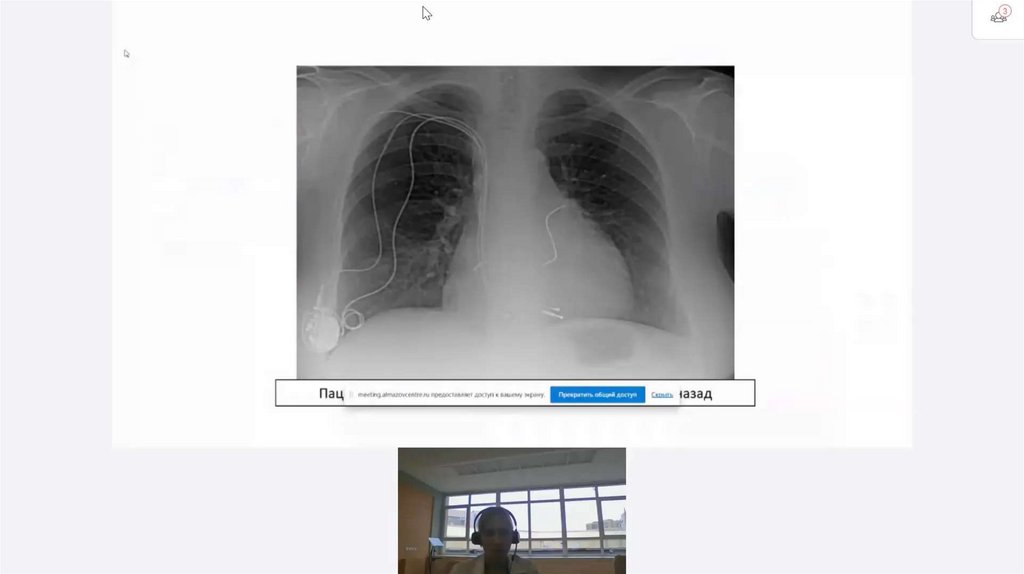

Курация пациентов с имплантированными кардиоустройствами: принципы и трудности